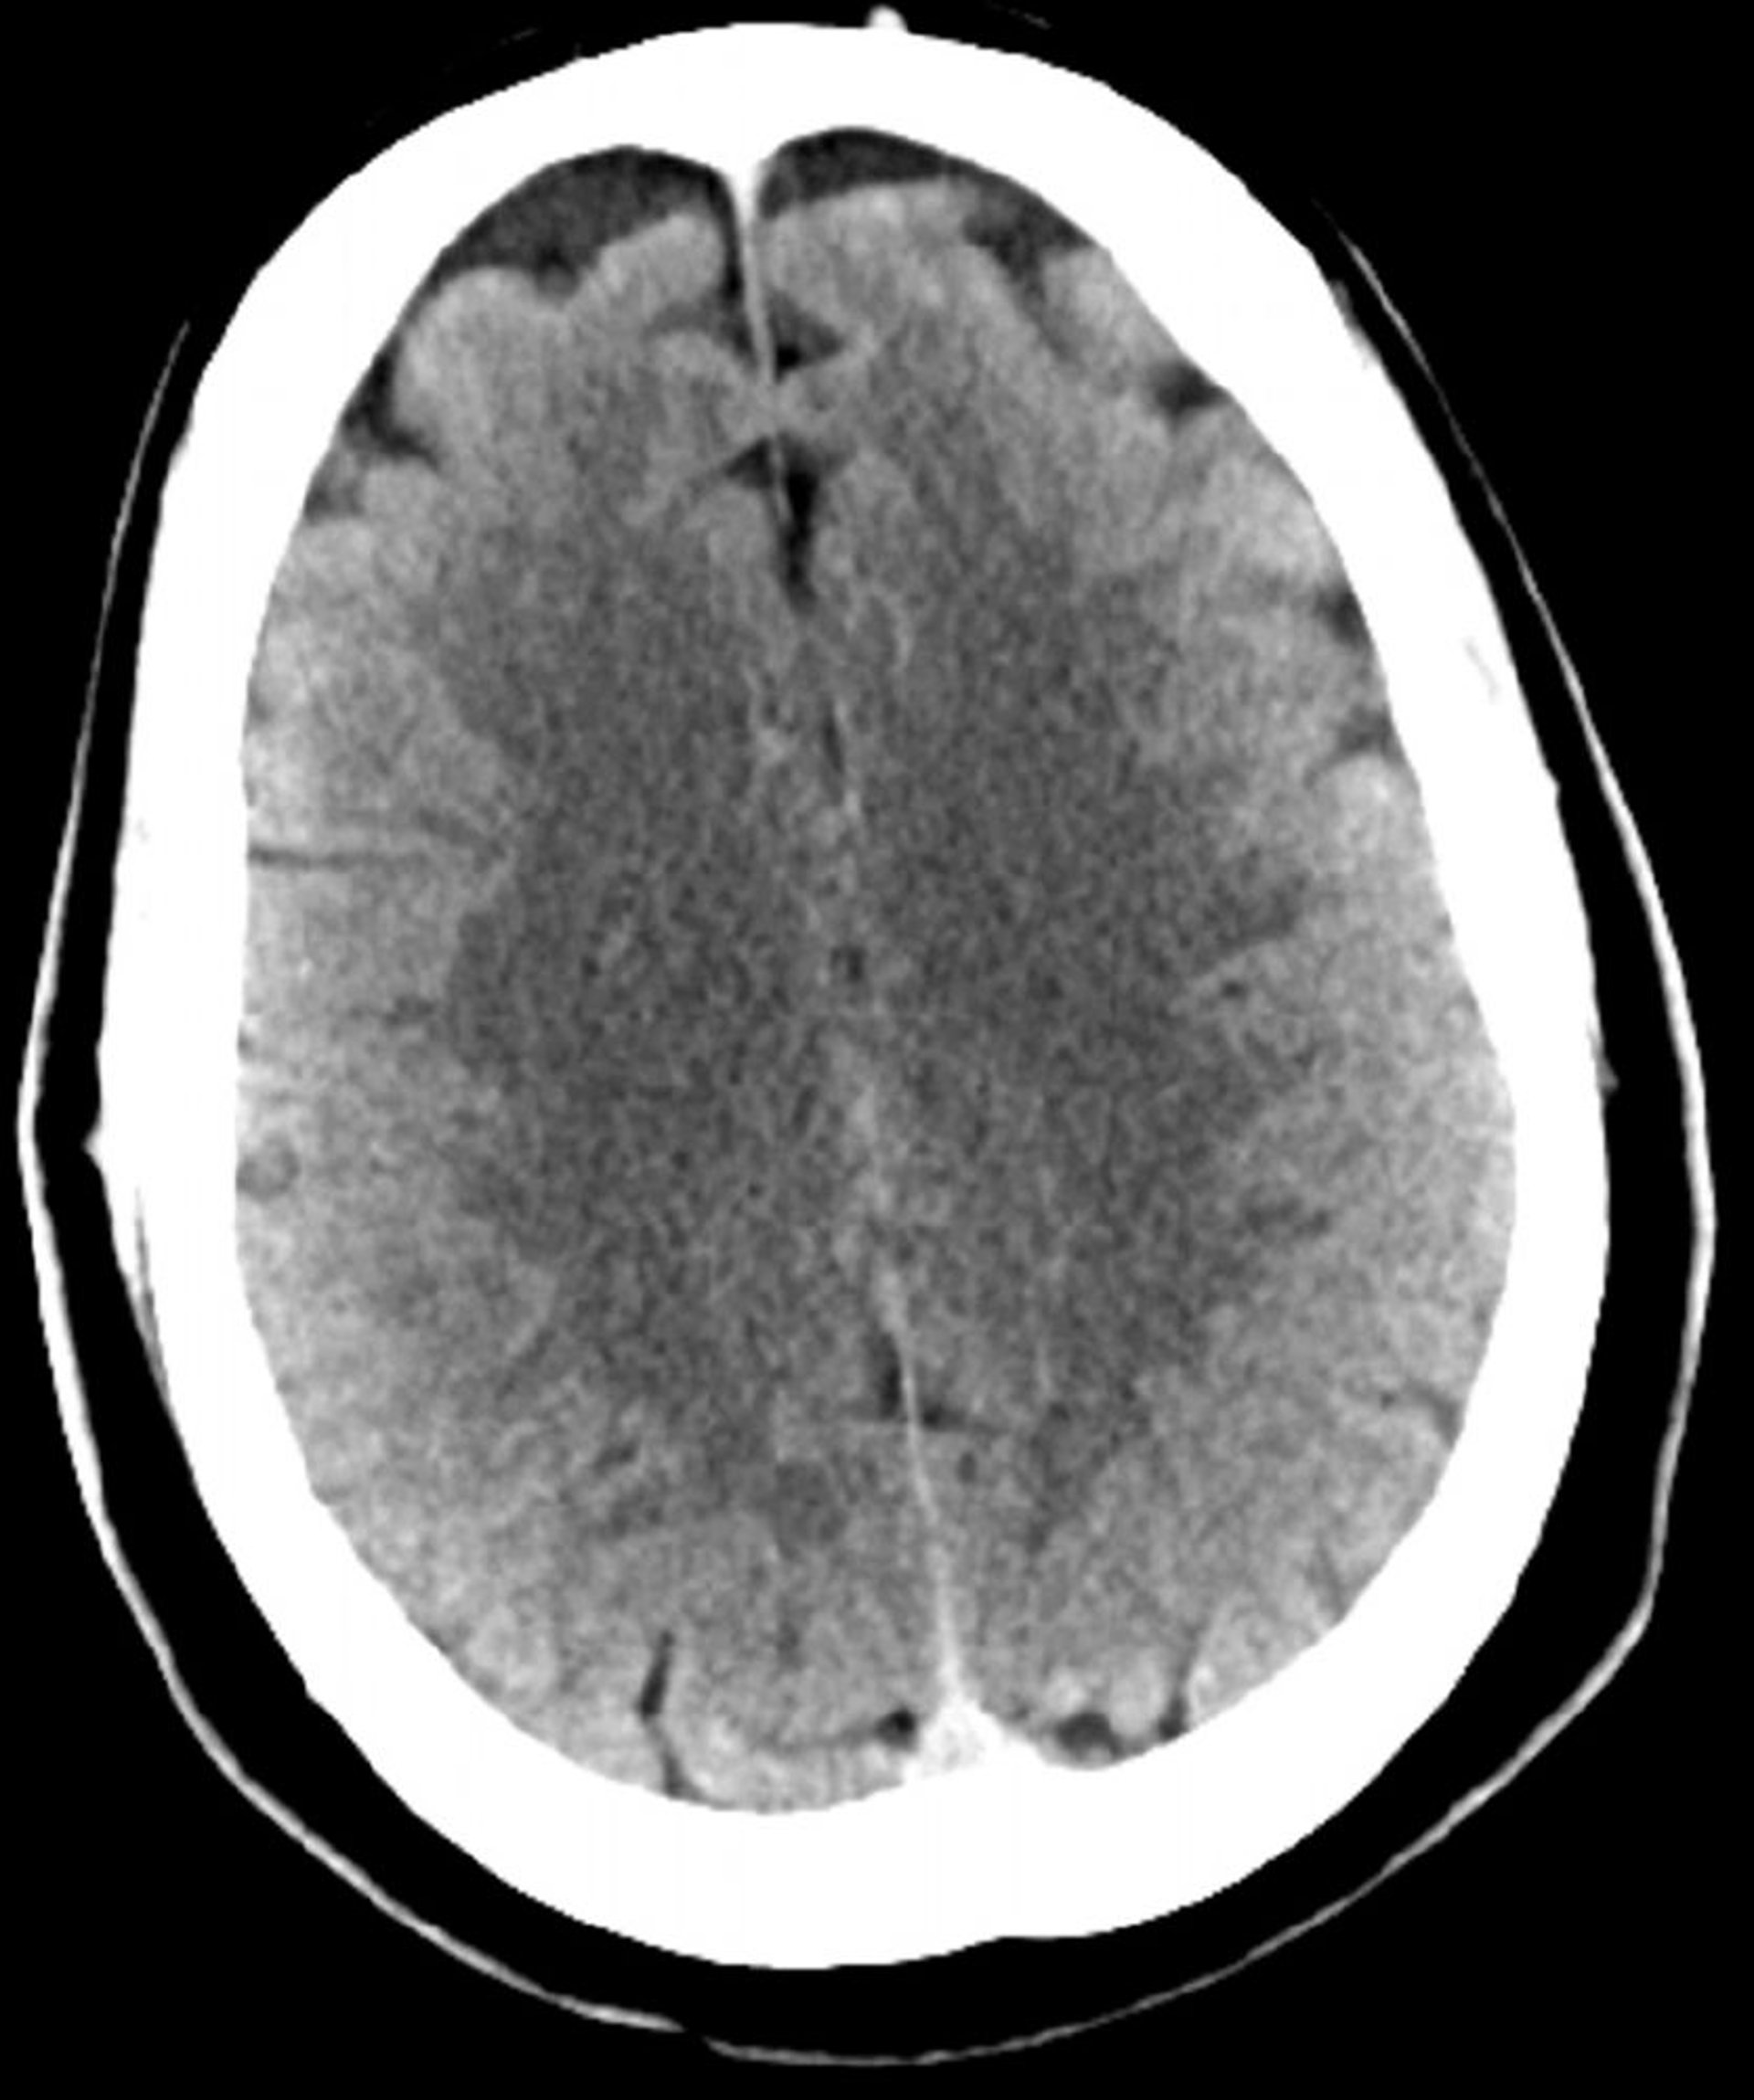

Tomografía computarizada craneal normal (adulto, 30 años)–diapositiva 2

Esta imagen es una tomografía computarizada craneal normal correspondiente a un adulto joven de 30 años de edad. No hay hemorragia o líquido intra- o extra axial. Se conserva la diferenciación gris-blanco. El patrón del surco es normal.